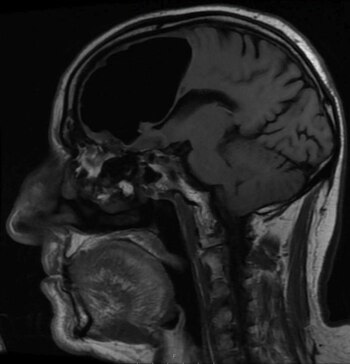

La sorpresa llevó luego de realizarle una tomografía y una resonancia magnética. No podían creerlo: prácticamente todo el lóbulo frontal derecho de este sujeto estaba desaparecido. Solo veían un espacio en blanco (o en negro).

Según determinaron, el paciente sufría de neumocefalia, la presencia de aire en el cráneo, una condición que suele presentarse en casos de cirugía al cerebro, infecciones o heridas faciales, aunque con burbujas o espacios de aire mucho más pequeños.

En este caso, la cavidad llegaba a medir casi nueve centímetros de largo en su parte más grande, algo difícil de encontrar en los libros de historia médica.

La causa más probable, según el equipo de investigadores, fue un tumor benigno formado en los senos paranasales del paciente, que erosionaron la base del cráneo y permitieron la formación de la cavidad.

"De lo que hablé con especialistas, parece ser que ha crecido durante meses o años. Cuando el paciente tosía, estornudaba o aspiraba, probablemente estaba empujando pequeñas cantidades de aire a su cabeza", explicó Brown.